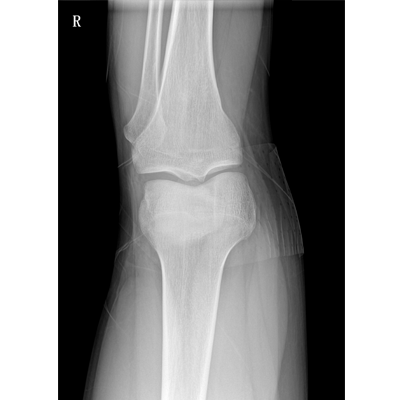

用于影像科、急診室、病房、ICU、手術(shù)室等多場景應(yīng)用。

● 數(shù)字化無線平板成像,操作簡便,成像質(zhì)量高